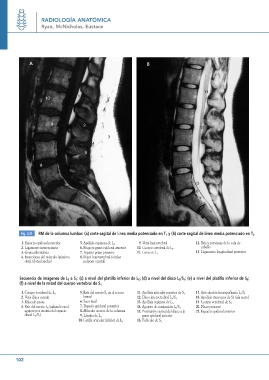

Fig. 3.21 RM de la columna lumbar: (a) corte sagital de línea media potenciado en T1 y (b) corte sagital de línea media potenciado en T2

1. Espacio epidural posterior 5. Apófisis espinosa de L4 9. Vena basivertebral 12. Raíces nerviosas de la cola de

6. Paquete graso epidural anterior caballo

2. Ligamento interespinoso 10. Cuerpo vertebral de L2

7. Espacio graso presacro 11. Cono en L1 13. Ligamento longitudinal posterior

3. Grasa subcutánea

8. Disco intervertebral (núcleo

4. Inserciones del músculo latissimo pulposo central)

dorsi (dorsal ancho)

Secuencia de imágenes de L5 a S1: (c) a nivel del platillo inferior de L5; (d) a nivel del disco L5/S1; (e) a nivel del platillo inferior de S1;

(f) a nivel de la mitad del cuerpo vertebral de S1

1. Cuerpo vertebral de L5 5. Raíz del nervio S1 en el receso 11. Apófisis articular superior de S1 17. Articulación interapofisaria L5/S1

2. Vena ilíaca común lateral 12. Disco intervertebral L5/S1 18. Apófisis transversa de S1 (ala sacra)

13. Apófisis espinosa de L5

3. Músculo psoas 6. Saco tecal 14. Agujero de conjunción L5/S1 19. Cuerpo vertebral de S1

7. Espacio epidural posterior 15. Protrusión central del disco a la 20. Plexo presacro

4. Raíz del nervio L5 (saliendo en el 8. Músculo erector de la columna

agujero por encima del espacio 9. Lámina de L5 grasa epidural anterior 21. Espacio epidural anterior

discal L5/S1) 10. Carilla articular inferior de L5

16. Pedículo de S1